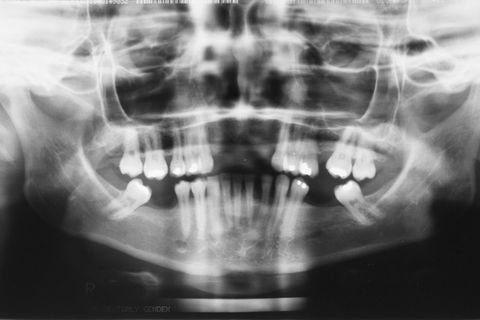

Radiografia Panorâmica inicial

Paciente do sexo feminino, 32 anos e 10 mêses de idade, com ausência dos incisivos centrais e laterais superiores, associado a um defeito ósseo vestibular côncavo. Realizamos planejamento reverso, ou seja, enceramento diganóstico prévio para avaliação do defeito ósseo em termos de quantidade e do posicionamento final das próteses. A paciente foi submetido a um enxerto ósseo autógeno do ramo ascendente lado direito e fixação dos blocos ósseos na área receptora, com fixação dos mesmos através de parafusos de fixação com cabeça expandida Neodent. Após 6 meses foram instalados 4 implantes Neodent.